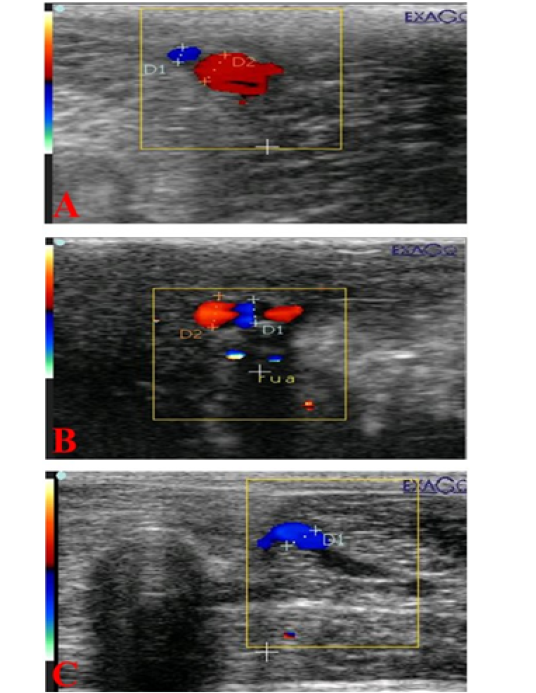

Ultrasonograms showing internal pudendal artery (I Pu.A.) (A), dorsal penile artery (Do Pe.A) (B), and deep penile artery (De Pe.A) (C), diameters (mm) in dogs suffered from TVT.

Mean ±SD internal pudendal artery (I Pu.A) (A), dorsal penile artery (Do Pe.A) (B), and deep penile artery (De Pe.A) (C) cross-sectional diameters (mm) during the first and second week before and after treatment by vincristine compared to control group.